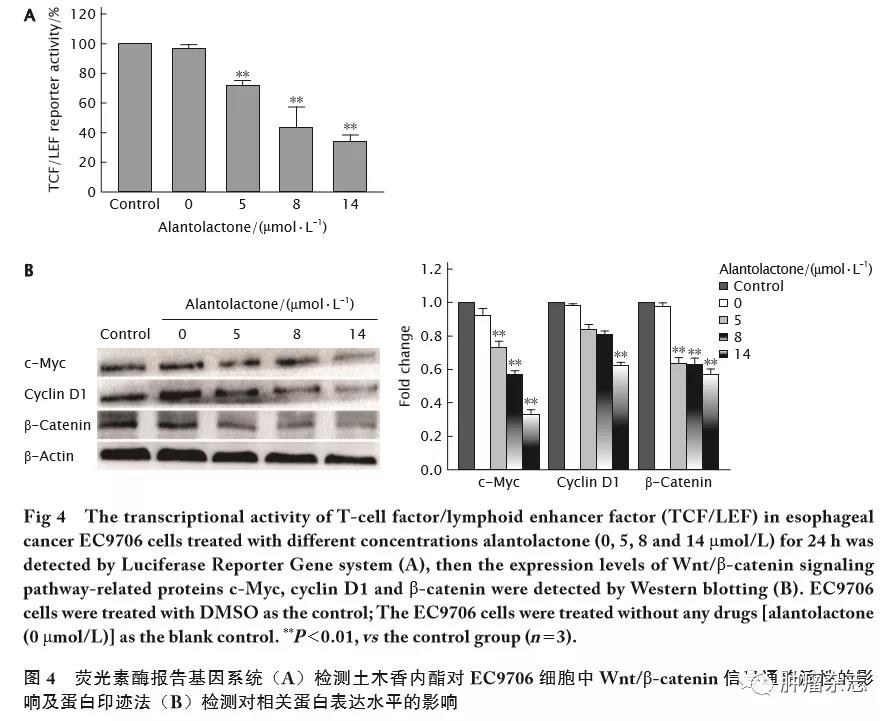

土木香内酯抑制食管癌EC9706细胞的增殖、迁移和侵袭并促进其凋亡王紫洁,胡 庆,陈 欢,李 婷,李 强,邓明明Alantolactone inhibits pr...